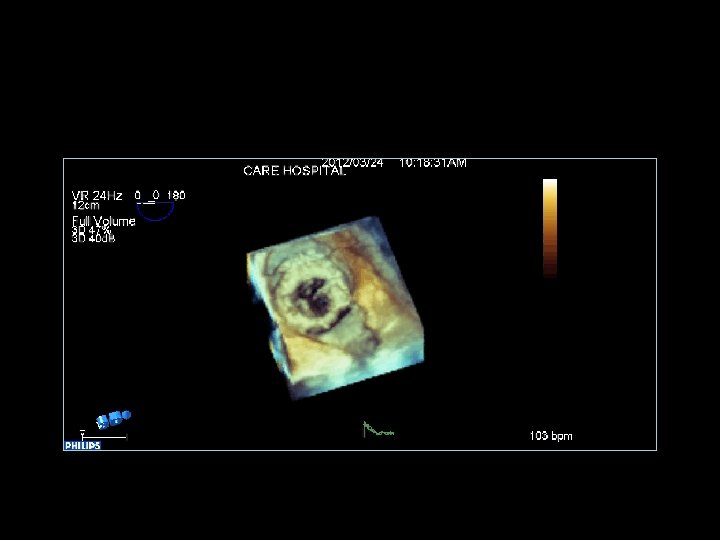

Anjali Bhattacharya MVR ( Tilting disc) Pro Valve dysfunction Pre and Post Lytic (Rx)